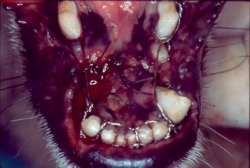

En el caso de la gingivitis, se clasifica según el tejido presente como “Gingivitis simple” en la cual la encía libre y papilar se encuentra hiperémica y sangrante; “Gingivitis hiperplásica” cuando la encía se encuentra con un aumento muy considerable en su tamaño y presenta un tejido inflamatorio hiperémico, sangrante e hiperplásico; y “Gingivitis hiperplásica fibrosa” cuando la encía está muy aumentada de tamaño y con una gran cantidad de tejido fibroso que se caracteriza por no ser hiperémico ni sangrante, sino que es de color rosa muy claro e inclusive hasta blanco y muy duro. Una de las características de las gingivitis hiperplásica y la gingivitis hiperplásica fibrosa es la presencia de bolsas periodontales falsas, ya que al medir la profundidad del surco este aparece aumentado, pero es debido al aumento del tamaño de la encía libre y papilar y no a la perdida de estructura ósea alveolar.

Haz CLICK sobre la imagen para ver descripción.